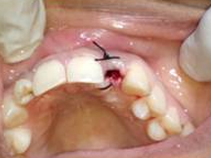

After Punch Cut

Placement of Bone Grafting

Drilling for Implant

Implant with bone Graft

Suturing done

Bone Graft in Extraction Socket

Use of Bone Graft & GTR membrane for an Implant

GTR Membrane on Bone Graft

Suturing after Bone Grafting